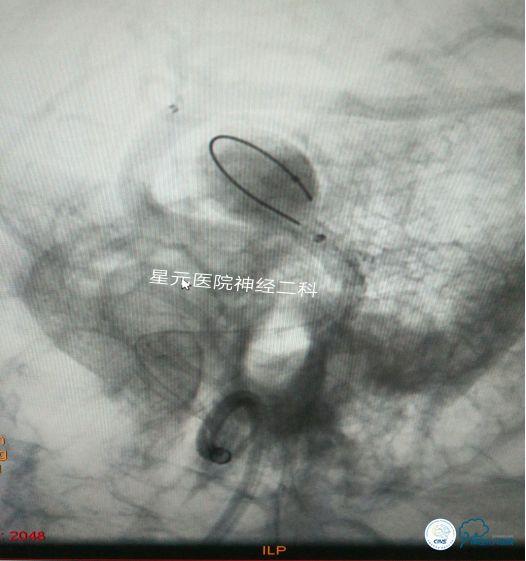

方案三:支架辅助双导管弹簧圈栓塞技术

➤回撤微导管A,支架保持不动,通过微导管B在瘤体底部眶额支开口方向小范围内进行弹簧圈的半释放,将眶额支开口处用弹簧圈充填!

➤通过微导丝将微导管A输送至瘤体腔内,然后通过微导管A进行对瘤顶部其余空间弹簧圈的缓慢致密栓塞。

➤将微导管B内的弹簧圈缓慢退出,造影证实,眶额支开口良好,血流通畅,将回收的弹簧圈通过微导管A再次进行致密充填!

➤栓塞完毕后,缓慢回撤微导管A,通过Naviven造影,了解充填情况。最后熔断释放支架。术毕,患者安返病房!

术后3天!痊愈出院!留影为证!汇报完毕!